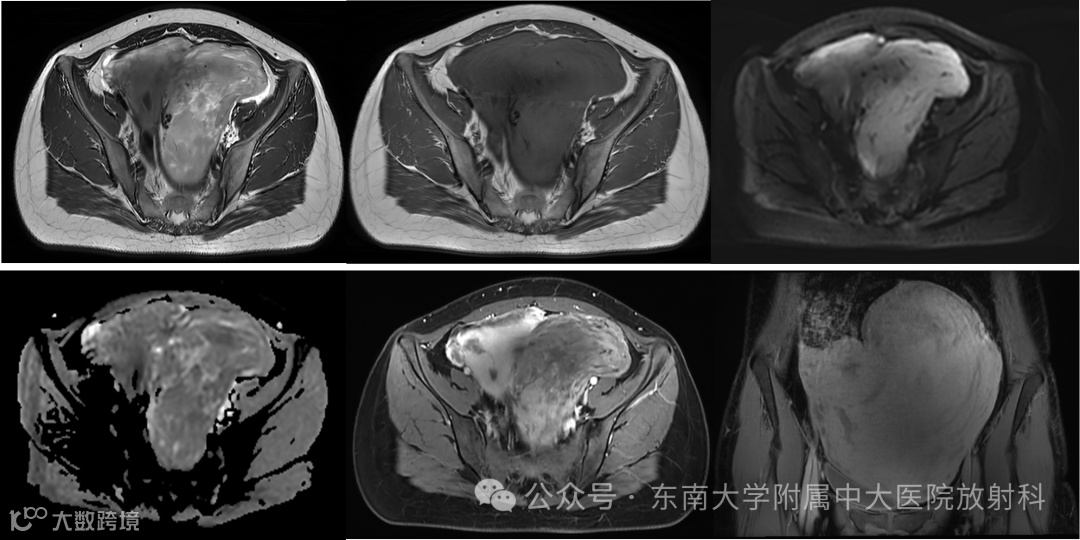

病例1

性别:女 年龄:28岁 主诉:发现盆腔包块 2 周余

现病史:患者平素月经规律,量中,无痛经,2周前体检发现盆腔包块,遂至我院就诊。B超,盆腔偏左侧混合性包块,宫颈多发囊肿。肿瘤指标:甲胎蛋白:1.65ng/ml,癌胚抗原:0.998ng/ml,糖链抗原125:7.42U/ml,糖链抗原153:3.61U/ml,人附睾分泌蛋白4:34.70pmol/L。患者偶有下腹坠胀感,无异常阴道流血流液,无同房后出血,无腹痛腹胀。现患者为求进一步诊治至我院就诊,门诊拟“盆腔肿物”收住入院

影像学表现